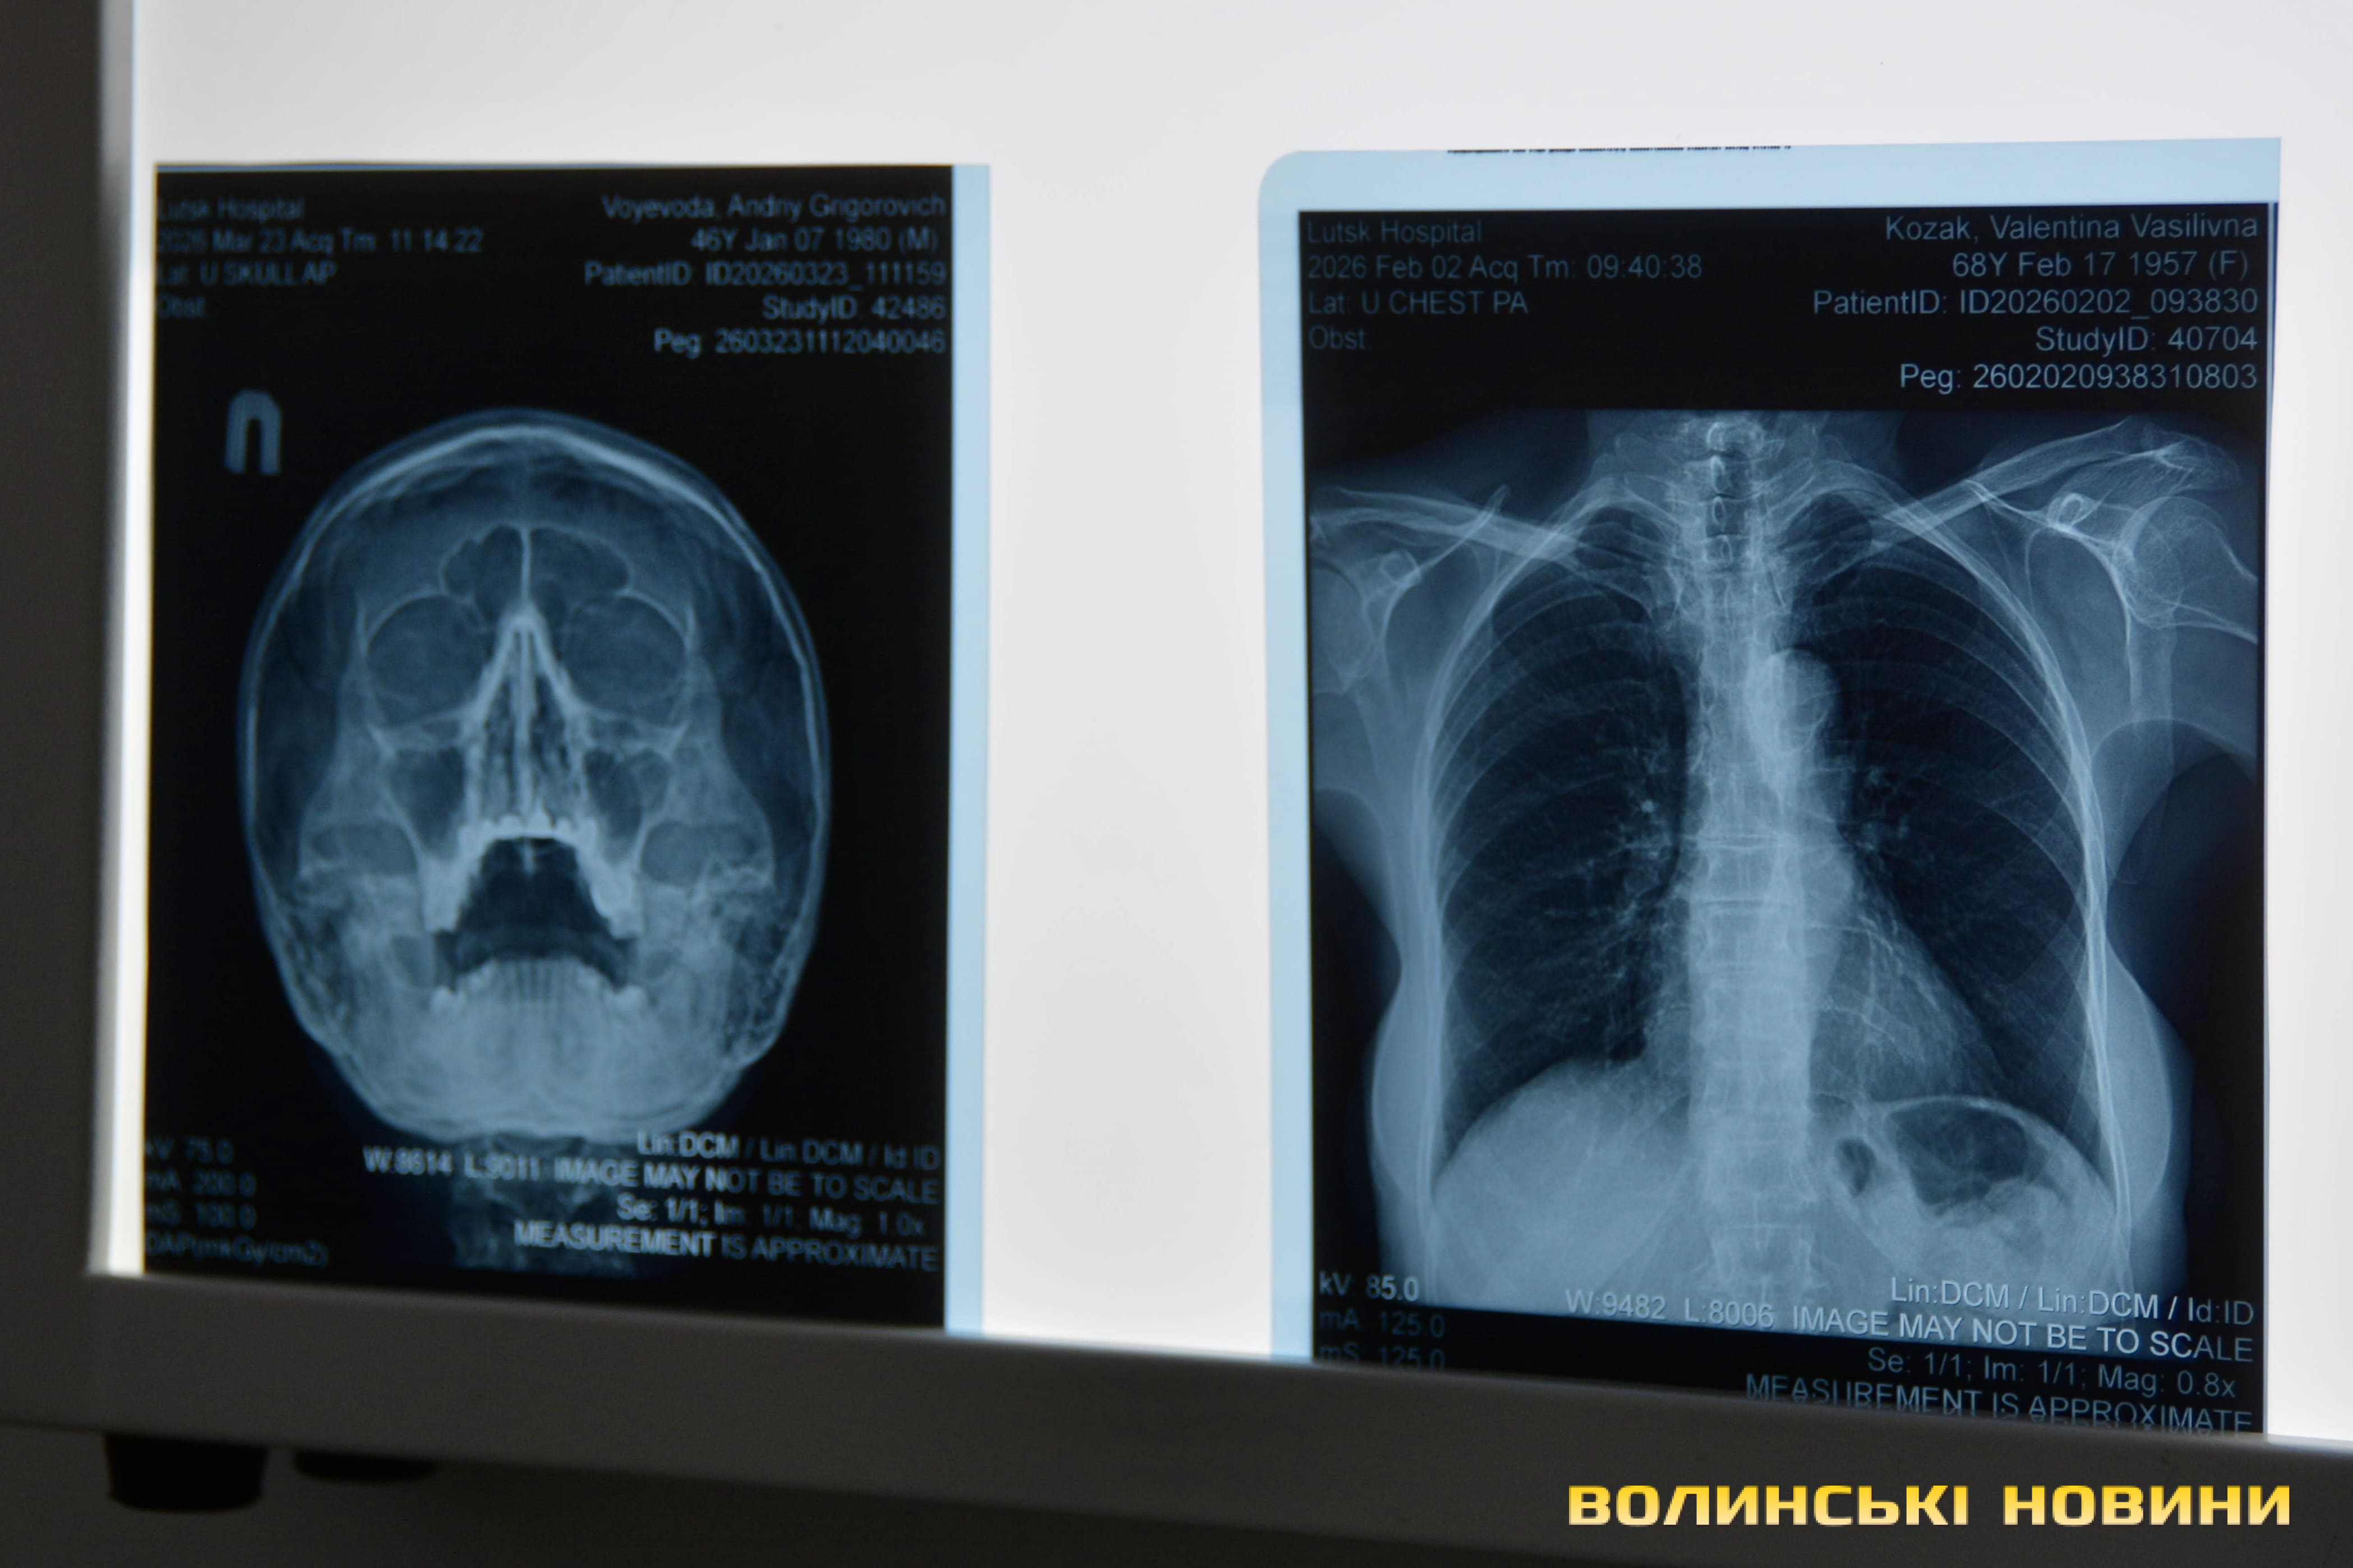

Щодо результатів обстеження в пересувному флюорографі, то, як прокоментувала Наталія Чурсіна, в більшості випадків у людей виявляють не туберкульоз, а інші патології. До слова, завдяки вбудованому штучному інтелекту таке обладнання швидко надає інформацію про наявні захворювання в людини, яка проходить обстеження.Рентгенологічне відділення

«Завдяки рентгенографії ми можемо діагностувати і онкологію, і пневмонію, і певні зміни в організмі. Наприклад, під час виїзду в Торчинській громаді було обстежено 48 людей. Туберкульозу не виявлено, однак виявлено одну пухлину та одну пневмонію. А ще в 19 людей помітили зміни, які свідчать про наявність інших патологій. Такий результат пов’язаний передусім із тим, що ми обстежуємо саме людей із групи ризику. Це люди віком 60+, маломобільні категорії населення, люди з ВІЛ-інфекцією, цукровим діабетом та інші. Часто саме цим людям з огляду на різноманітні обставини важко дістатися до лікаря, тому вони особливо потребують нашої уваги», – сказала Наталія Чурсіна.